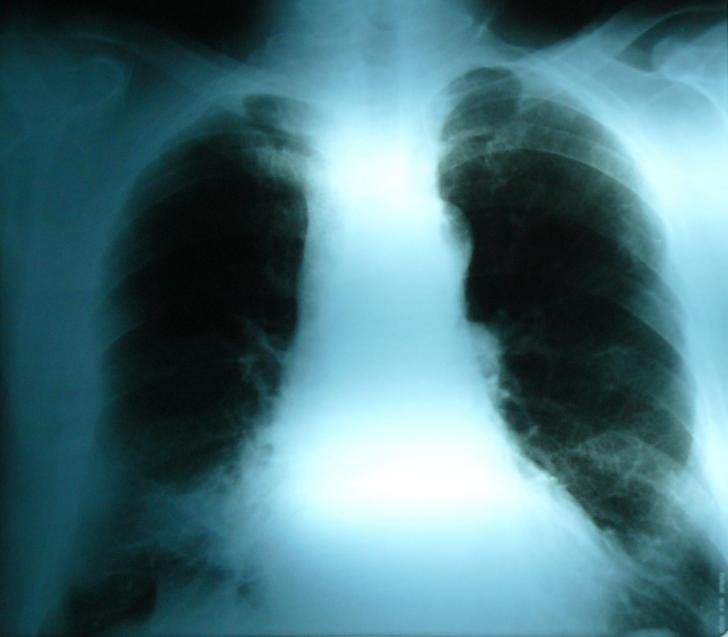

ANEVRISM SACCIFORM DE CROSA AORTICA LA UN PACIENT ASIMPTOMATIC SI PROBLEMELE DE CONDUITA TERAPEUTICA

ANEVRISM SACCIFORM DE CROSA AORTICA LA UN PACIENT ASIMPTOMATIC SI PROBLEMELE DE CONDUITA TERAPEUTICA Definitie: Anevrismul de aorta reprezinta dilatarea aortei de peste 1,5 ori diametrul aortei corespunzator segmentului respectCiteste tot ... 1147 cuvinte

Dimensiune mica

+ cu imagini |

BOLILE APARATULUI CARDIO-VASCULAR

BOLILE APARATULUI CARDIO-VASCULAR Aparatul cardio-vascular este format din inima, vase sanguine si limfatice. Inima este un organ tetracameral (doua atrii si doua ventricule), care pompeaz�Citeste tot ... 820 cuvinte

Dimensiune mica

+ cu imagini |